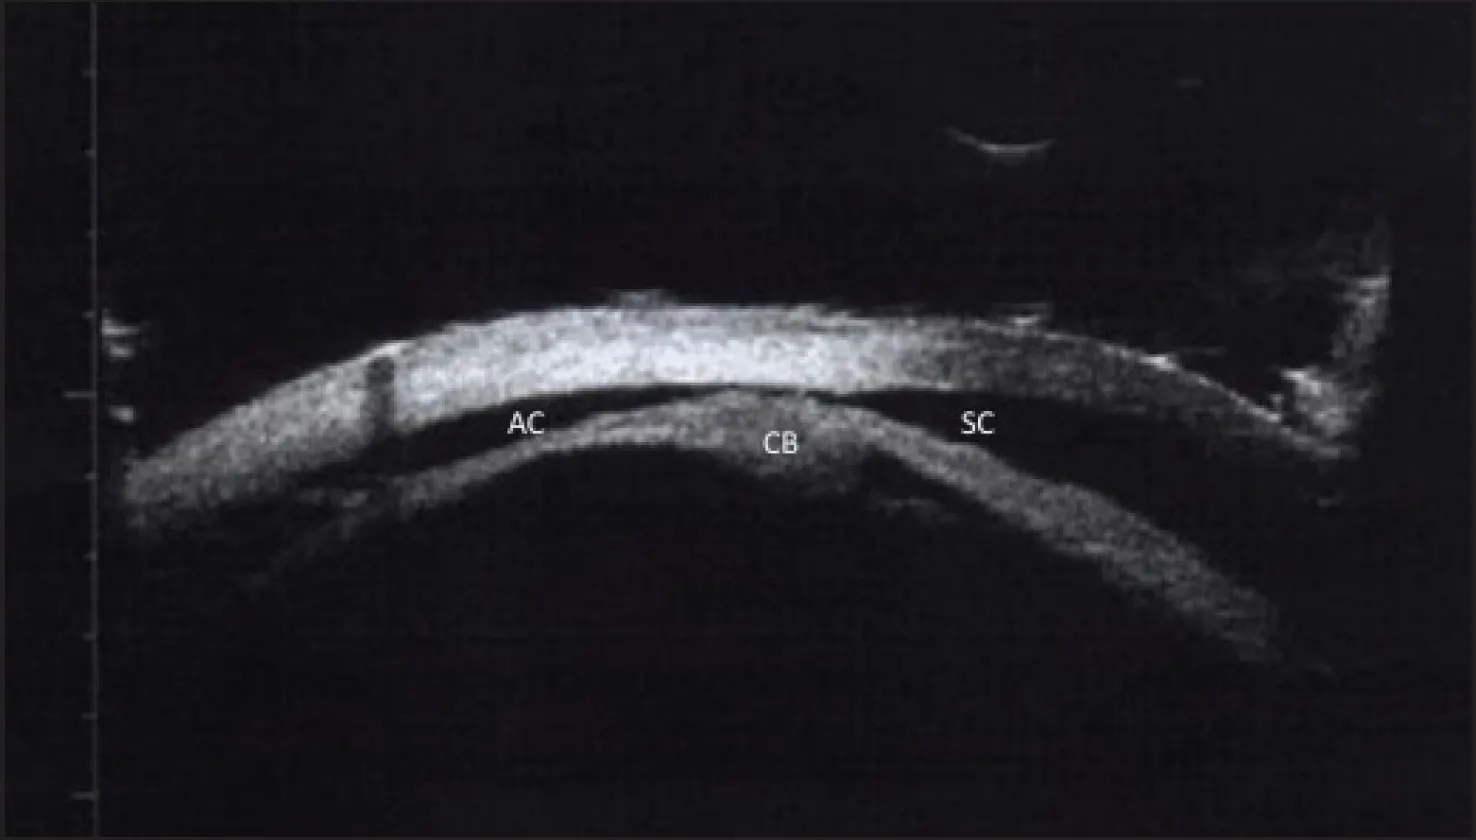

Ultrasound biomicroscopy (UBM) is an important complementary method for diagnosing and evaluating the circumferential extent of a cyclodialysis cleft. On imaging, the cleft appears as a distinct, hypoechoic space between the anterior chamber and the suprachoroidal space (Figure 3). UBM can be crucial for preoperative planning and the postoperative management of large clefts as well as for monitoring the resolution of small clefts.

Figure 3. UBM is used to visualize a hypoechoic cyclodialysis cleft, superior to the ciliary body (CB) and a conduit between the anterior chamber (AC) and suprachoroidal space (SC), in relation to anterior segment structures.